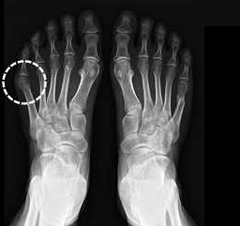

처음엔 별문제 없다가도, 세시간 정도 라이딩하고 나면 사진에 표시된 부위에 통증이 오는데요

원인이 뭔지 잘 모르겠습니다ㅠㅠ

본인 엑스레이 사진이신가요?

잘은 모르지만 왼쪽 뼈만 바깥쪽으로 휜걸봐서 라이딩시 그쪽 관절에 과도한 무게로 압박되어 그런건 아니실런지

그냥 엑스레이 보다가 생각난 의견입니다

아 제 엑스레이는 아니구요ㅎㅎ

저 부분을 정확히 말로 표현하기가 어려울듯해서 구글링에서 퍼왔습니다